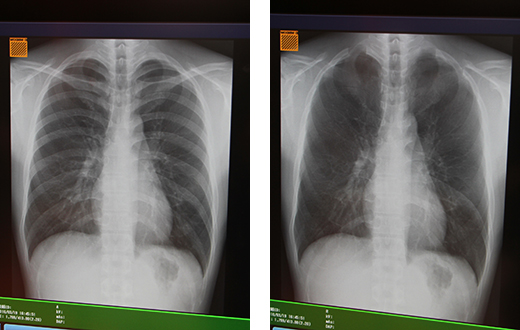

また,近くバージョンアップ予定のDRX-Revolutionの新しいソフトウエアに搭載される機能として,“ボーン・サプレッション”を紹介した。ボーン・サプレッションでは,胸部画像において画像処理によって1回の撮影画像からワンボタンで骨部分を除去した画像が作成でき,軟部組織の観察をサポートする。

新ソフトウエアのボーン・サプレッション機能。元画像(左)と骨除去画像(右)